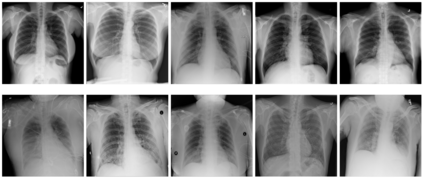

With the ongoing rise of machine learning, the need for methods for explaining decisions made by artificial intelligence systems is becoming a more and more important topic. Especially for image classification tasks, many state-of-the-art tools to explain such classifiers rely on visual highlighting of important areas of the input data. Contrary, counterfactual explanation systems try to enable a counterfactual reasoning by modifying the input image in a way such that the classifier would have made a different prediction. By doing so, the users of counterfactual explanation systems are equipped with a completely different kind of explanatory information. However, methods for generating realistic counterfactual explanations for image classifiers are still rare. Especially in medical contexts, where relevant information often consists of textural and structural information, high-quality counterfactual images have the potential to give meaningful insights into decision processes. In this work, we present GANterfactual, an approach to generate such counterfactual image explanations based on adversarial image-to-image translation techniques. Additionally, we conduct a user study to evaluate our approach in an exemplary medical use case. Our results show that, in the chosen medical use-case, counterfactual explanations lead to significantly better results regarding mental models, explanation satisfaction, trust, emotions, and self-efficacy than two state-of-the-art systems that work with saliency maps, namely LIME and LRP.